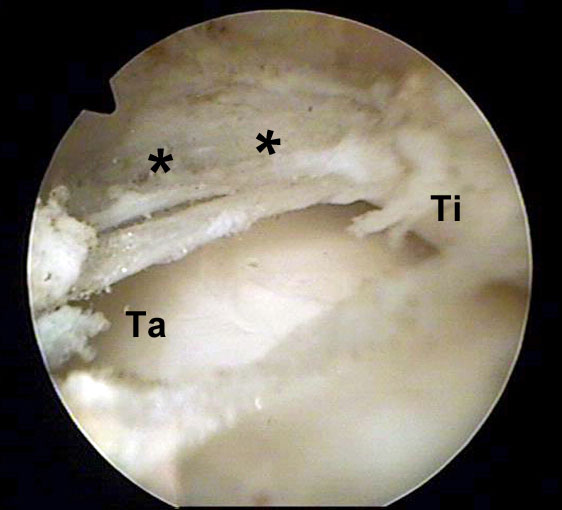

Abbildung 8, Video 3

Hypertrophie der Synovia und der Gelenkkapsel (*) im anterolateralen Kompartiment am linken OSG. Das Gewebe rutscht bei Bewegungen und unter Belastung in den Gelenkspalt zwischen Tibia (Ti) und Talus (Ta) und verursacht schmerzhafte Einklemmungen. Es erfolgt eine Resektion mit einer bipolaren Radiofrequenzsonde über das anterolaterale Standardportal. Auf einen ausreichenden Abstand der Radiofrequenzsonde zur Knorpeloberfläche ist zu achten, um iatrogene Hitzeschäden zu vermeiden. Hilfreich ist eine Arbeitsrichtung vom Talushals ausgehend nach kraniolateral. Durch maximale Dorsiflexion des Fußes weitet sich das ventrale Kompartiment und das Gewebe ist weniger gespannt. Hierdurch vergrößert sich der Arbeitsraum und wird die Resektion vereinfacht. Darüber hinaus wird die Knorpeloberfläche des Talus von der Tibia bedeckt und geschützt.